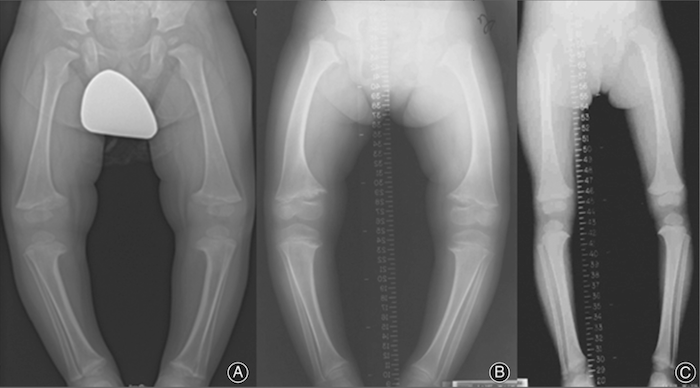

Fig.3. A: Genu varum em rapaz de 5 anos com curvatura das pernas; B: genu varum em rapariga de 7 anos; C: genu varum menos pronunciado em rapariga de 9 anos. Todas as crianças mostraram um alargamento das placas de crescimento associada à concavidade metafisária, que se assemelha ao raquitismo. Fonte: Wiley Online Library